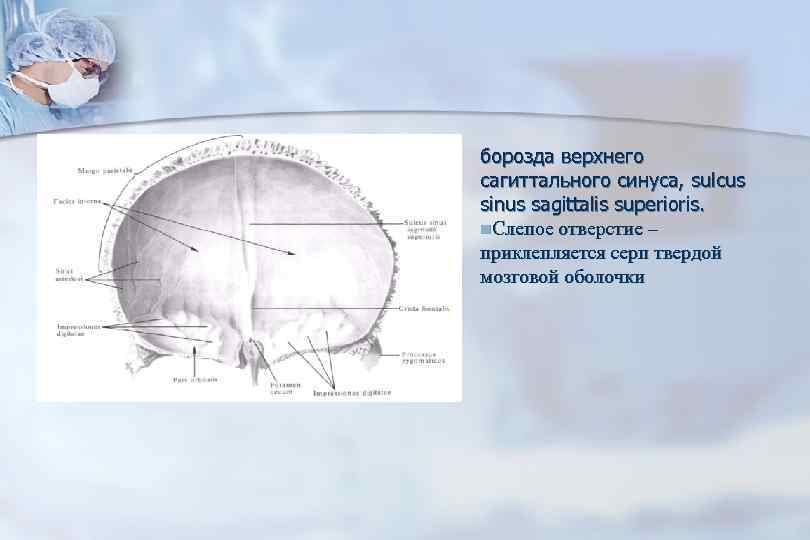

Анатомические изображения срединной сагиттальной линии черепа